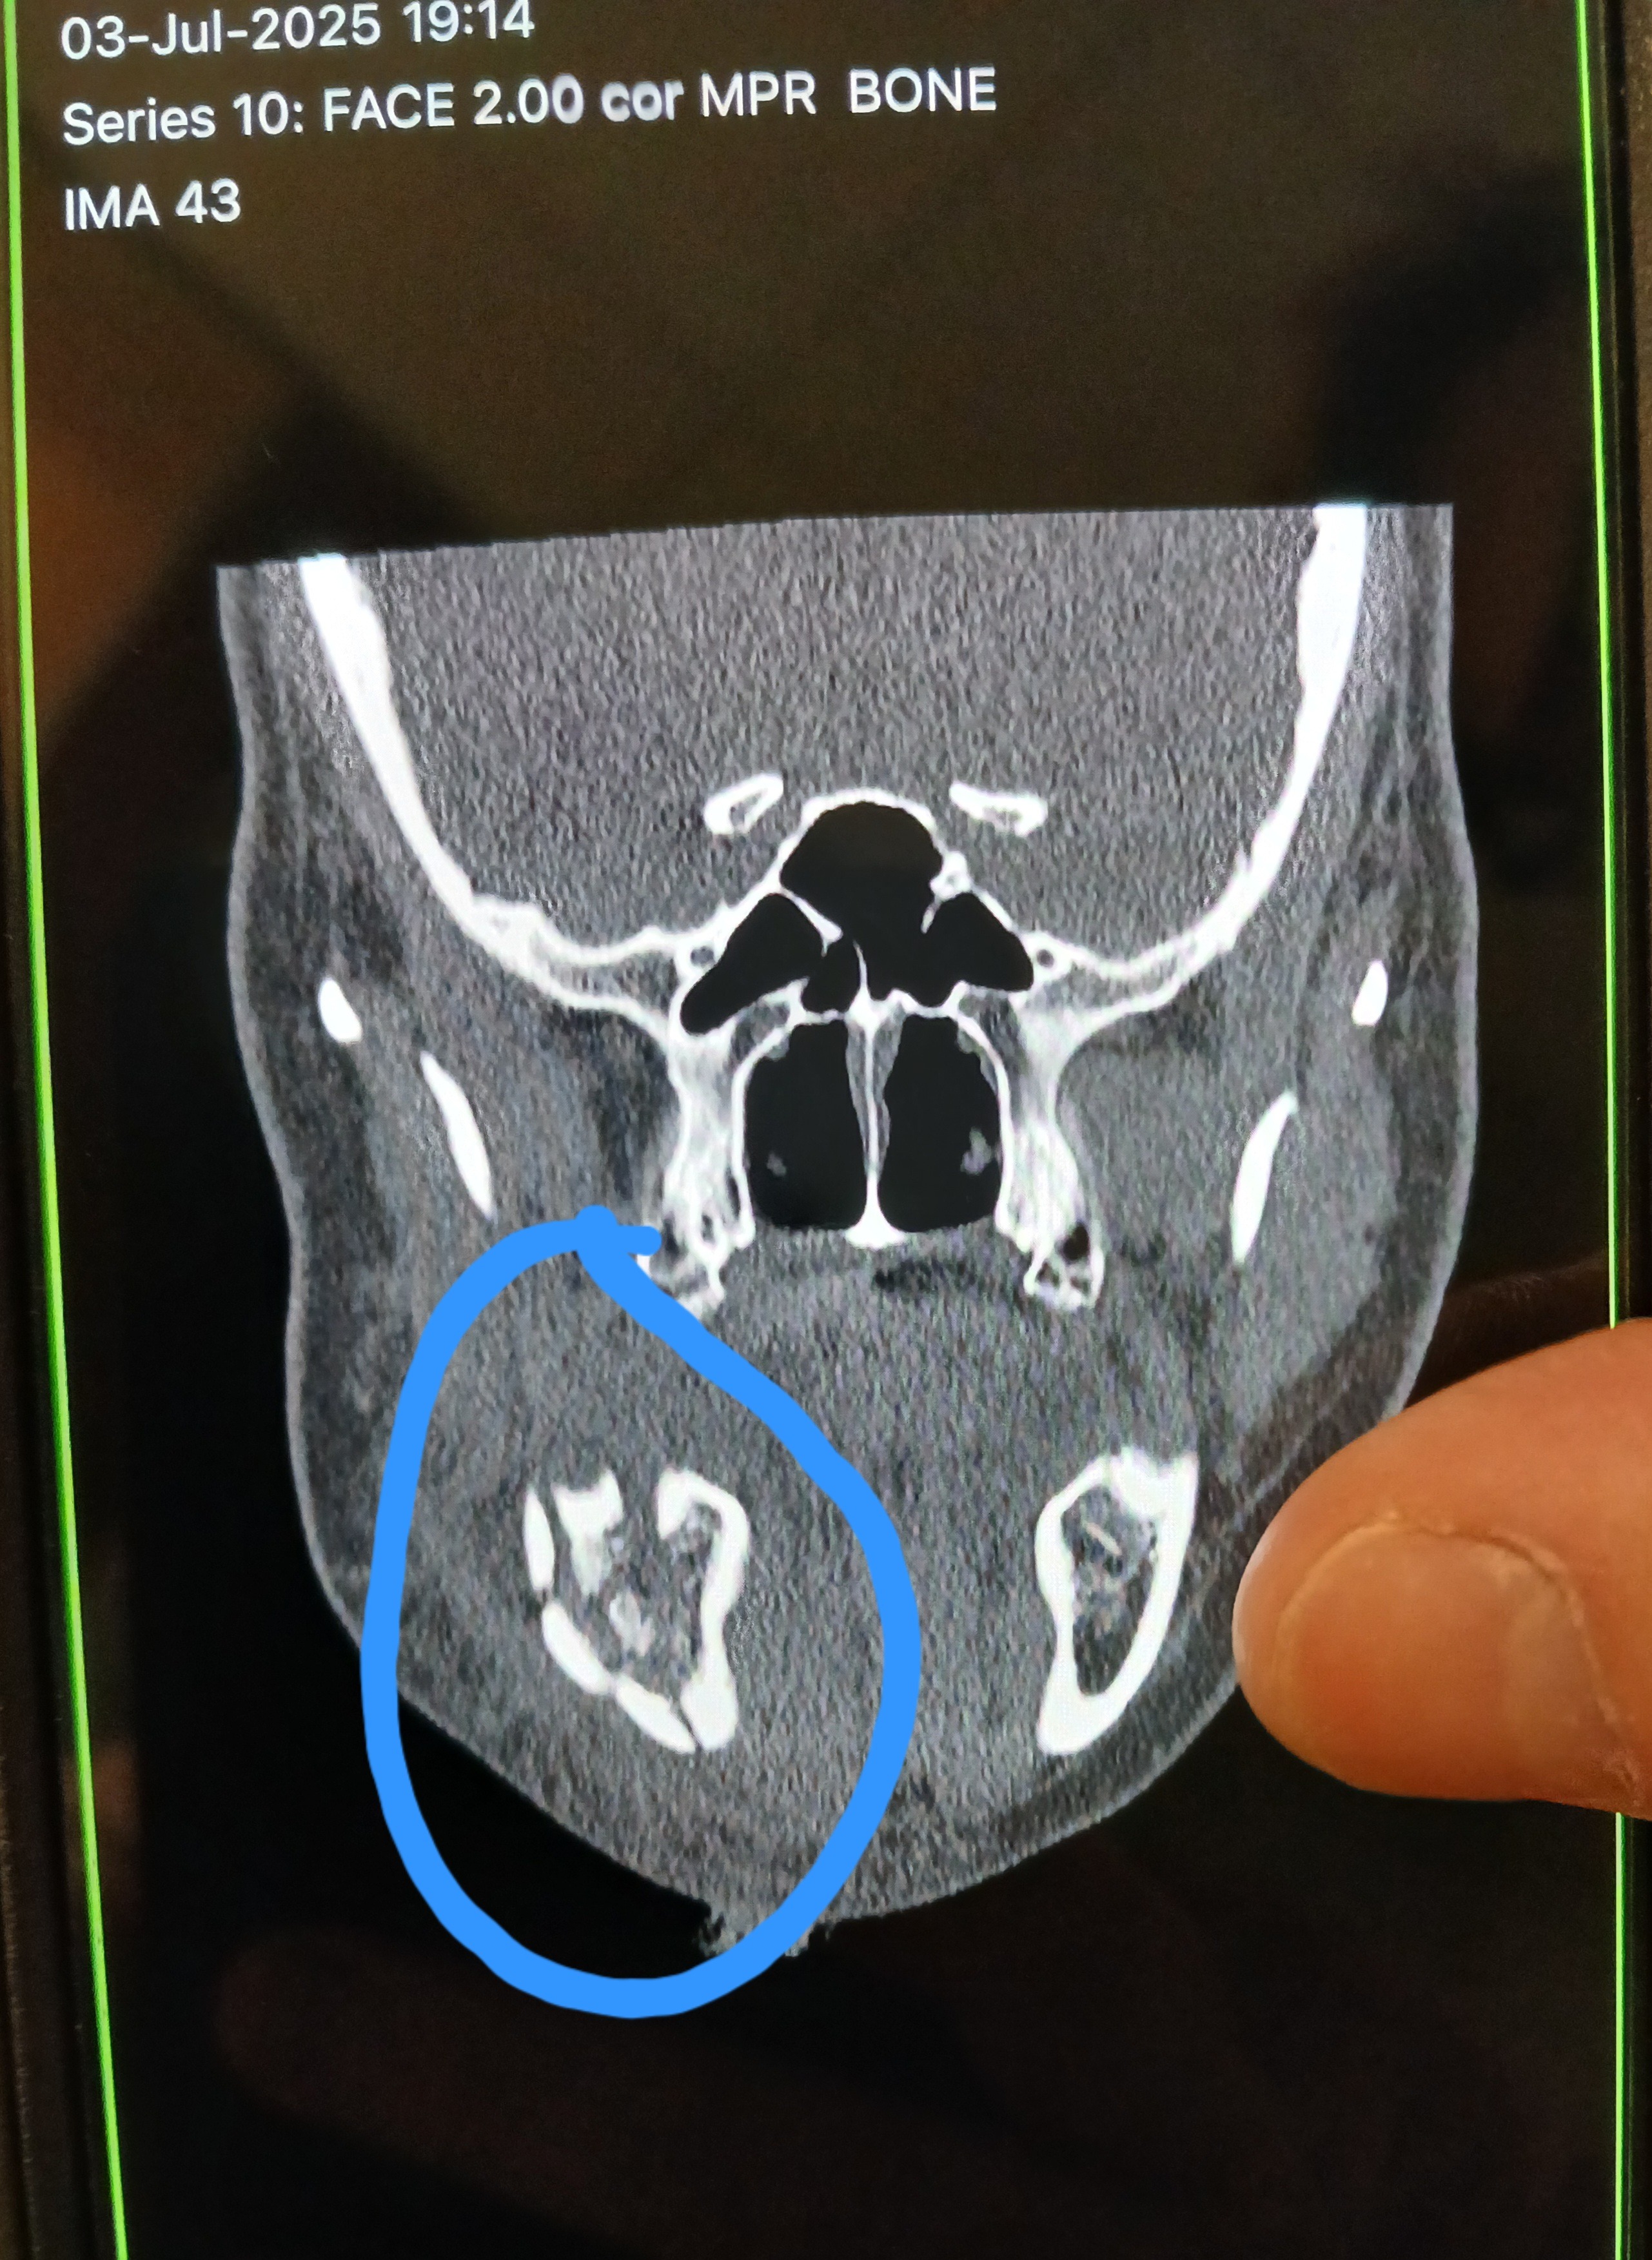

Raising funds to help support my sisters new liquid/soft diet and travels to many doctor appointments. There's also her husbands missed time from work to bring her to and from appointments. Thursday July 3rd, she was struck by lightening....and SURVIVED! After the jolt lifted her off the ground, she landed on her chin, breaking it in two spots. Enough so that three plates were needed to reconstruct her jaw. I'm looking to help her fund her new "diet" orders of soft and liquid nutrients like: fruits, veggies, smoothie king, boost, ensure, & other soft foods she can swallow easily. If you can help her and her family out, that would be awesome and very much appreciated! All funds will go towards her nutrition and healing process. Thank you for the prayers and God Bless!!!!